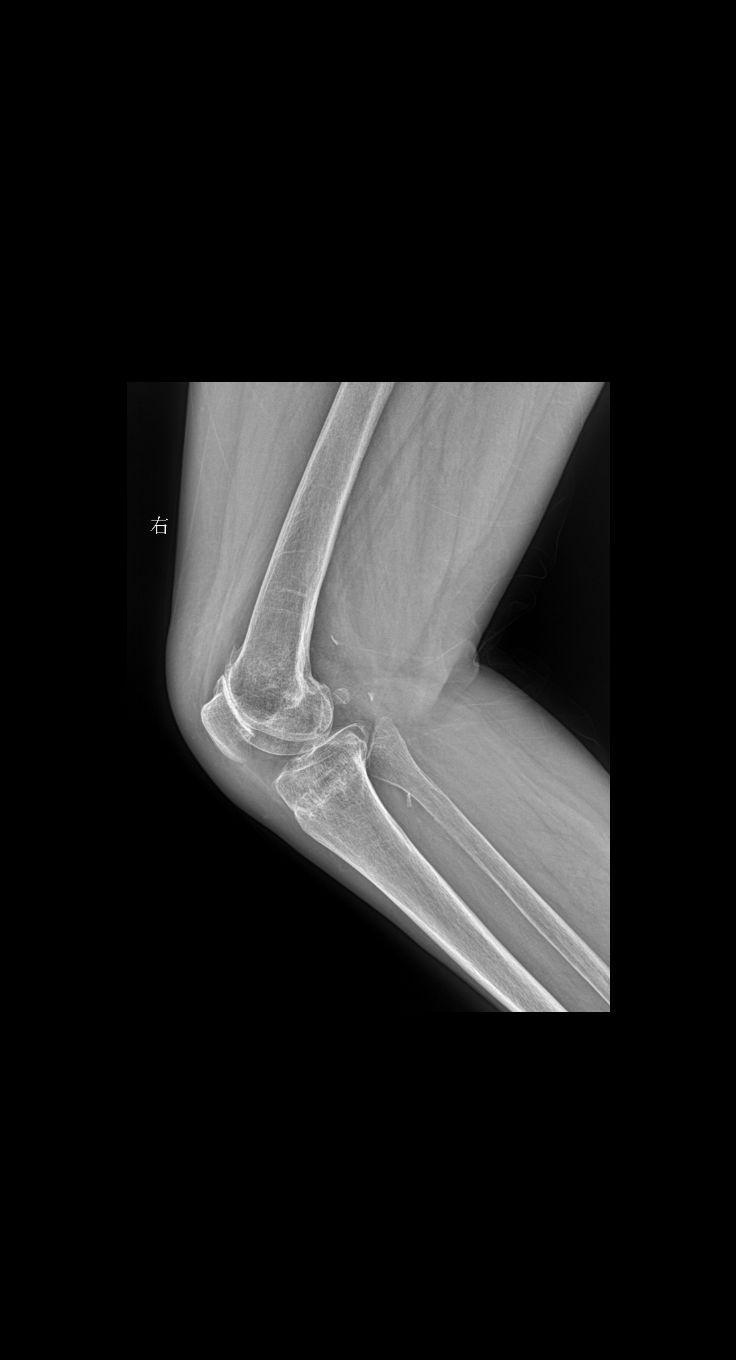

行走膝盖 脚底疼痛就诊 女69岁 考虑什么问题?